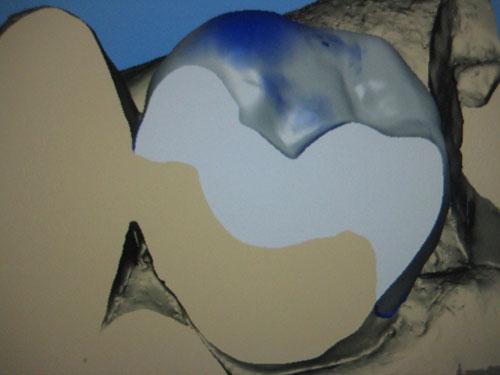

Visualisation de l'intrados en mode "Cut"

Les données sont envoyé en Wifi à l'unité d'usinage CEREC MCXL situé sur place. Un bloc Empress CAD A3 C14 est inséré dans l'unité. L'usinage dure une dizaine de minute.